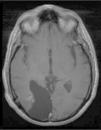

El xantoastrocitoma pleomórfico (XAP) es un tumor astrocitario raro, de localización más frecuente superficial en hemisferios cerebrales de niños y adultos jóvenes. Se trata de un tumor de bajo grado que tiene un pronóstico relativamente favorable; sin embargo, se han descrito pacientes con progresión maligna. Presentamos así un caso inusual de un varón de 54 años con una tumoración multiquística parietooccipital derecha con extensión intraventricular. Tras la exéresis quirúrgica el estudio histológico mostró una lesión con células pleomórficas, cúmulos de lípidos en su citoplasma, cuerpos granulares intensamente eosinófilos, núcleos únicos bien delimitados y positividad inmunohistoquímica frente a sinaptofisina, proteína gliofibrilar ácida (GFAP), proteína S-100, vimentina y CD56 de forma focal. Tras descartar otras entidades, como metástasis por carcinoma de células grandes y una lesión primaria tipo astrocitoma subependimario de células grandes, se diagosticó de XAP. A los 9 meses de seguimiento el paciente presentó una extensa recidiva tumoral local considerada irresecable, con deterioro neurológico progresivo y signos radiológicos de progresión maligna, confirmados histológicamente mediante la realización de una biopsia cerebral que demostró cambios respecto a la lesión inicial que incluían focos de necrosis, mayor actividad mitótica (5×10 campos de gran aumento) e índice de proliferación celular medido con la tinción nuclear de Ki67 del 10%. El presente caso ilustra la extensión intraventricular, así como un comportamiento agresivo no característico de estas lesiones (similar a un astrocitoma anaplásico o glioblastoma primario), exigiendo un tratamiento quirúrgico óptimo inicial con seguimiento estrecho clínico-radiológico, considerando el potencial de transformación maligna del XAP.

Pleomorphic xanthoastrocytoma (PXA) is a rare, low-grade astrocytic tumour that usually occurs in the superficial cerebral hemispheres of children and young adults. Although it has a relatively favourable prognosis, malignant progression of these tumours has been described. Therefore, we present an unusual case of a 54-year-old male with a right, multicystic, parietooccipital tumour extending through the ipsilateral ventricle. After surgical resection, histological examination revealed a lesion with pleomorphic cells, cytoplasmic lipidisation, intensely eosinophilic granular bodies, well-delimitated unique nuclei and focal, positive immunoreactivity for synaptophysin, glial fibrillary acidic protein (GFAP), S-100 protein, vimentin and CD56. Once other tumours, such as giant cell metastatic carcinoma or primary lesion like subependymal giant cell astrocytoma, were ruled out, a final diagnosis of XAP was established. After a follow-up period of 9 months, the patient suffered an extensive and local tumour relapse considered inoperable, with progressive neurological deterioration and radiological findings of malignant progression. The brain biopsy procedure revealed anaplastic changes, including necrosis foci, higher mitotic activity (5×10 high-power fields) and a 10% proliferation index measured by Ki67 labelling. The present case showed intraventricular extension and a more aggressive behaviour, both uncommon in these tumours (similar to anaplastic astrocytoma or glioblastoma multiforme), thus demanding an initial, optimal surgical treatment with close clinical and radiological follow-up, due to the high potential for malignant transformation of XAPs.